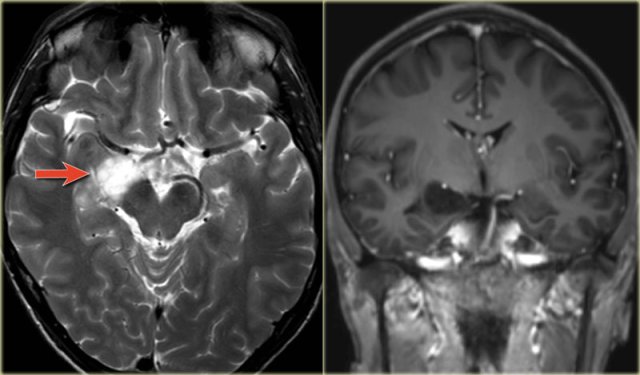

The coronal T2WI and FLAIR images show right-sided mesial temporal sclerosis.

Notice the volume loss, which indicates atrophy and causes secondary enlargement of the temporal horn of the lateral ventricle.

The high signal in the hippocamous reflects gliosis.

The images show mesial temporal sclerosis with a hyperintense and shrunken hippocampus (red arrows), and secondary enlargement of the left temporal horn of the left laterale ventricle.

Also notice associated subcortical hyperintensity in the left temporal lobe indicating focal cortical dysplasia.